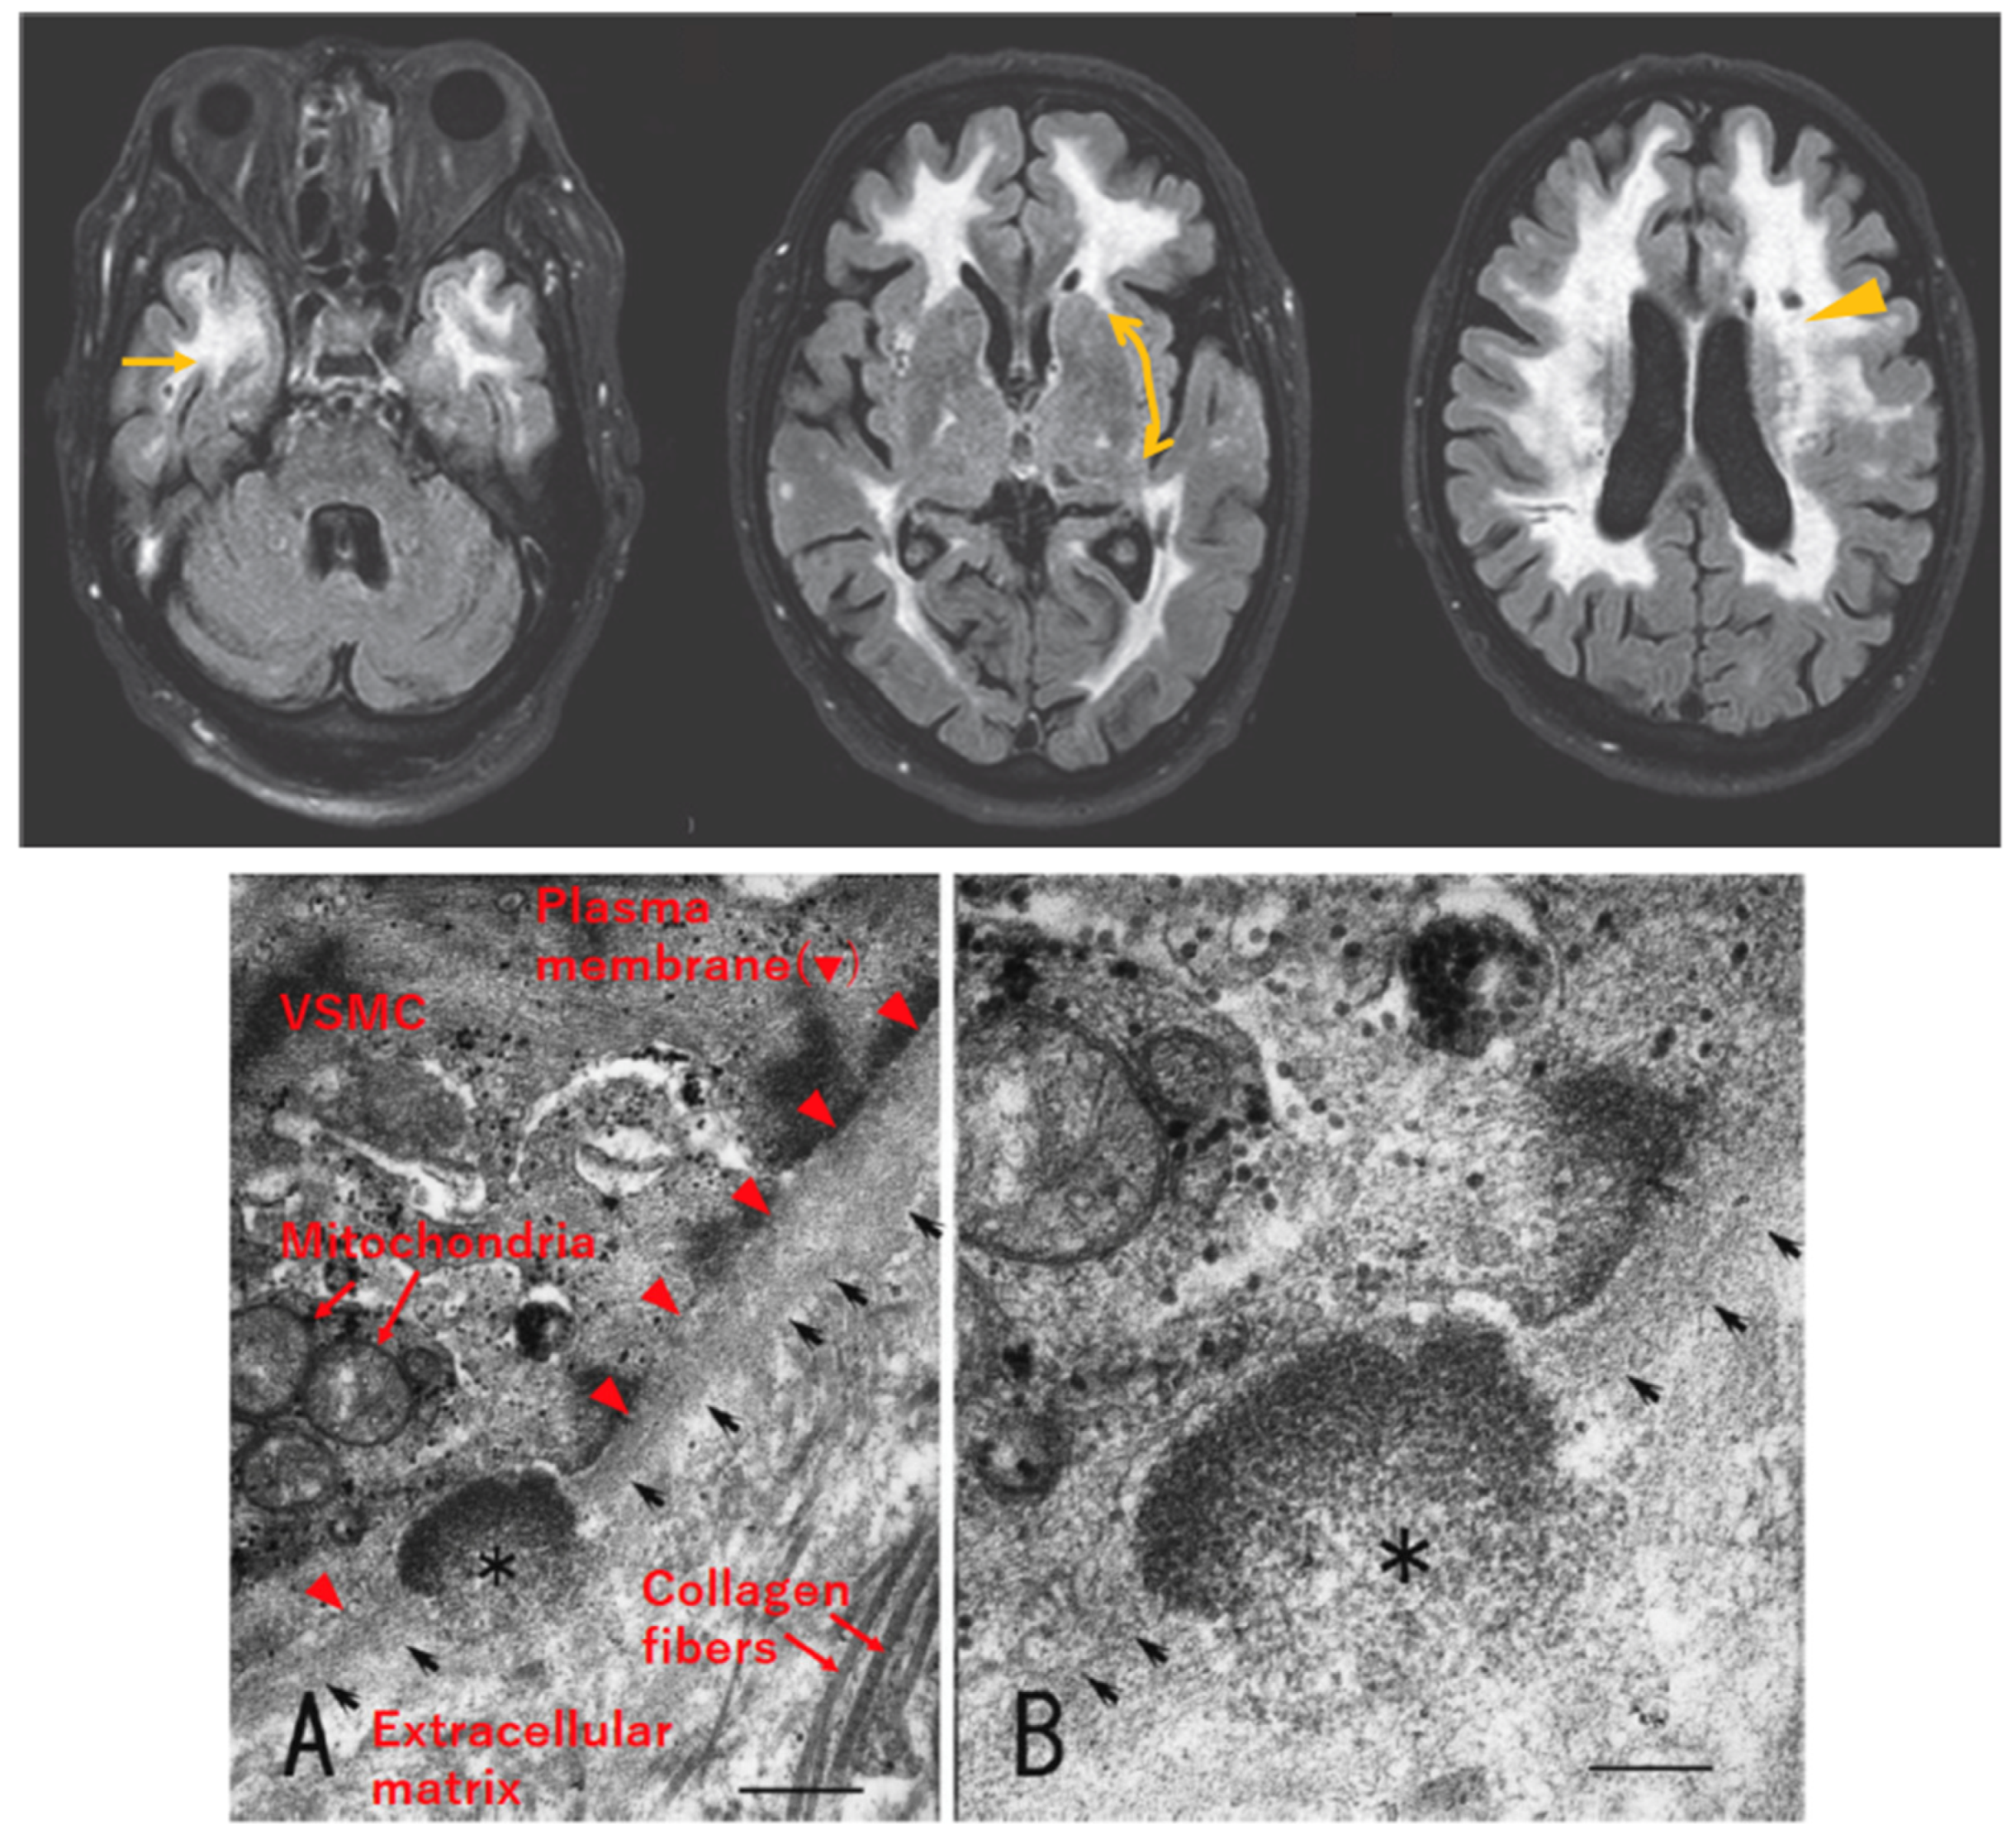

- Lorenzi, T.; Ragno, M.; Paolinelli, F.; Castellucci, C.; Scarpelli, M.; Morroni, M. CADASIL: Ultrastructural insights into the morphology of granular osmiophilic material. Brain Behav. 2017, 7, e00624. [Google Scholar] [CrossRef] [PubMed]

- Yamamoto, Y.; Craggs, L.J.; Watanabe, A.; Booth, T.; Attems, J.; Low, R.W.; Oakley, A.E.; Kalaria, R.N. Brain microvascular accumulation and distribution of the NOTCH3 ectodomain and granular osmiophilic material in CADASIL. J. Neuropathol. Exp. Neurol. 2013, 72, 416–431. [Google Scholar] [CrossRef]

- Ishiko, A.; Shimizu, A.; Nagata, E.; Takahashi, K.; Tabira, T.; Suzuki, N. Notch3 ectodomain is a major component of granular osmiophilic material (GOM) in CADASIL. Acta Neuropathol. 2006, 112, 333–339. [Google Scholar] [CrossRef] [PubMed]